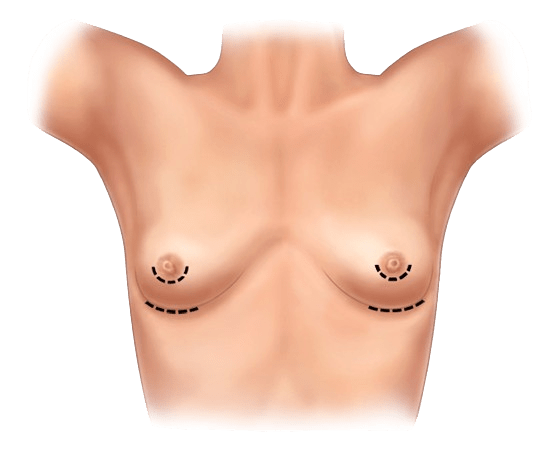

Göğüs implantını yerleştirmek için plastik cerrahınız, üç olası yerden birinde tek bir kesik yapacak:

- Göğüs altındaki kıvrım (inframammary)

- Koltuk altınızın altında (aksiller)

- Memenizin etrafında (periareolar)

Kesik yaptıktan sonra, cerrah göğüs dokunuzu göğüs duvarınızın en dış kası (pektoral kas) önünde veya arkasında bir cep oluşturacak. Cerrah, implantı bu cebe yerleştirecek ve memenizin ucunun arkasında merkezleyecektir. İmplant yerleştirildikten sonra, kesik genellikle dikişler, cilt yapıştırıcıları ve cerrahi bant ile kapatılır.